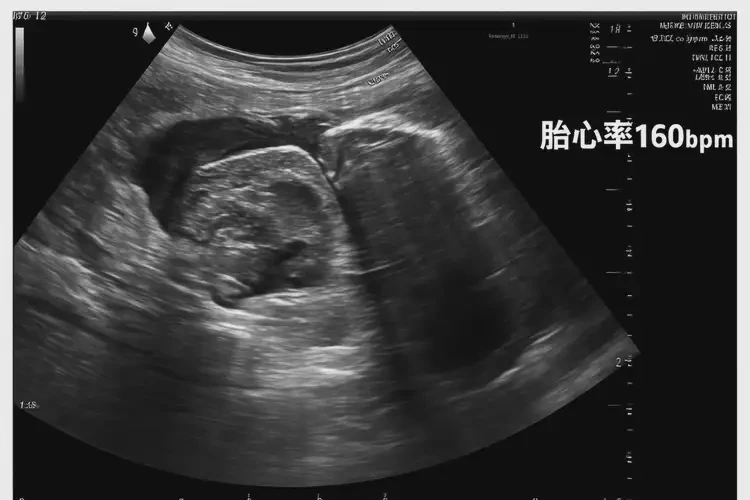

孕11周2天胎心率160左右有危險(xiǎn)嗎

160次/分鐘

孕11周2天的胎兒胎心率在160次/分鐘左右,通常屬于正常范圍。胎心率是指胎兒心臟每分鐘跳動的次數(shù),是評估胎兒健康狀況的重要指標(biāo)之一。在孕早期,胎心率通常較快,隨著孕周的增加,胎心率會逐漸減慢。

孕11周2天胎心率160左右有危險(xiǎn)嗎(圖1)